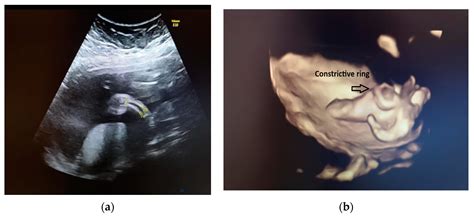

Early detection of Amniotic Band Syndrome through ultrasound is essential for timely intervention and better outcomes. *Amniotic Band Syndrome Ultrasound* involves detailed imaging of the fetus to identify the presence of fibrous bands and assess their impact on fetal development. This diagnostic tool is typically performed during routine prenatal check-ups, usually between 18 and 22 weeks of gestation.

• Imaging: A transducer is moved over the abdomen to capture images of the fetus. The ultrasound technician or radiologist will focus on areas where bands are likely to form, such as the limbs, head, and torso.

• Assessment: The images are analyzed to detect any signs of constriction, amputation, or other deformities caused by the bands.